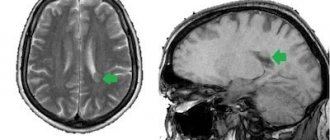

Желудочки головного мозга – это своеобразные полости в ткани мозга, которые предназначены для депонирования